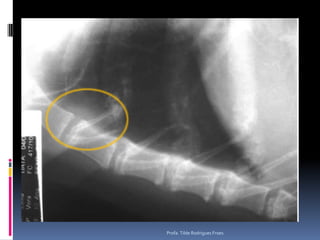

Exame radiográfico Esqueleto apendicular e  axialImportanteAlta freqüência – NEOPLASIAS ÓSSEASEsqueleto apendicular e axialOSTEOSSARCOMAAspectos radiográficosDiferenciais diagnósticosNão esquecer – radiografar o tórax – metástasesCuidados nessa interpretação – falsos negativos – lesões iniciaisProfa. Tilde Rodrigues Froes

Como diferenciar lesões ósseas Esqueleto ApendicularMalignas BenignasTipo de reação periostealPouco delimitadasMais expansivasTipo de perda ósseaBordos pouco precisosPerda da integridade da corticalZona de transiçãoIndefinidaLocalPoliostica x monosticaPiora na avaliação seriadaTipo de reação periostealMais delimitadaMenos expansivasTipo de perda ósseaBordo definidoNão altera a integridade da corticalZona de transiçãoDefinidaLocal Profa. Tilde Rodrigues Froes

Exame radiográfico Esqueletoapendicular e axialImportanteAlta freqüência – NEOPLASIAS ÓSSEASEsqueleto apendicular e axialOSTEOSSARCOMAAspectos radiográficosDiferenciais diagnósticosNão esquecer – radiografar o tórax – metástasesCuidados nessa interpretação – falsos negativos – lesões iniciaisProfa. Tilde Rodrigues Froes

Como diferenciar lesõesósseas Esqueleto ApendicularMalignas BenignasTipo de reação periostealPouco delimitadasMais expansivasTipo de perda ósseaBordos pouco precisosPerda da integridade da corticalZona de transiçãoIndefinidaLocalPoliostica x monosticaPiora na avaliação seriadaTipo de reação periostealMais delimitadaMenos expansivasTipo de perda ósseaBordo definidoNão altera a integridade da corticalZona de transiçãoDefinidaLocal Profa. Tilde Rodrigues Froes